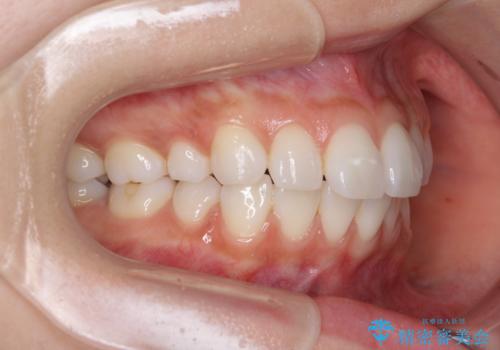

矯正治療の後戻り インビザラインによる再矯正治療

- 以前ワイヤー装置にて行った抜歯矯正の後戻りを気にして来院された患者様です。

前歯のデコボコにより、やや口元が突出した印象となっていたため、口元も引っ込めることとしました。

上下顎前歯に積極的にIPR(歯と歯の間を削る)を行い、インビザラインを用いて治療していくこととしました。

デコボコが解消されるのはもちろんのこと、突出感のあった前歯を引っ込めることができ、患者様には大変満足していただきました。